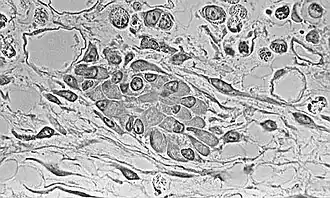

The process of intramembranous ossification starts when a small group of adjacent MSCs begin to replicate and form a small, dense cluster of cells that is called a nidus.[a] Once a nidus has been formed the MSCs within it stop replicating. At this point, morphological changes in the MSCs begin to occur: The cell body is now larger and rounder; the long, thin cell processes are no longer present; and the amount of Golgi apparatus and rough endoplasmic reticulum increases. Eventually, all of the cells within the nidus develop into, and display the morphologic characteristics of, an osteoprogenitor cell.[1]

At this stage of development, changes in the morphology of the osteoprogenitor cells occur: Their shape becomes more columnar and the amount of Golgi apparatus and rough endoplasmic reticulum increases. Eventually, all of the cells within the nidus develop into, and display the morphologic characteristics of, an osteoblast. Then the osteoblasts create an extracellular matrix containing Type-I collagen fibrils, which is osteoid. The osteoblasts, while lining the periphery of the nidus, continue to form osteoid in the center of the nidus. Some of the osteoblasts become incorporated within the osteoid to become osteocytes.[1]

At this point, the osteoid becomes mineralized resulting in a nidus consisting of mineralized osteoid that contains osteocytes and is lined by active osteoblasts. The nidus, that began as a diffuse collection of MSCs, has developed into woven bone, the most rudimentary bone tissue.[1]